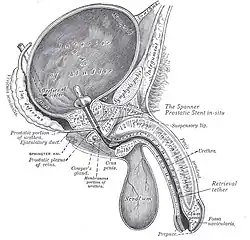

Prostatic stent

Prostatic stents are placed from the bladder through the prostatic and penile urethra to allow drainage of the bladder through the penis. This is sometimes required in benign prostatic hyperplasia.

A prostatic stent is used to keep the male urethra open and allow for the passage of urine in cases of prostatic obstruction and lower urinary tract symptoms (LUTS). There are two types of prostatic stents: temporary and permanent. Permanent stents, typically made of metal coils, are inserted into the urethra to apply constant gentle pressure and hold open sections that obstruct urine flow. They can be placed under anesthesia as an outpatient procedure but have disadvantages such as increased urination, limited incontinence, potential displacement or infection, and limitations on subsequent endoscopic surgical options. On the other hand, temporary stents can be easily inserted with topical anesthesia similar to a Foley catheter, and allow patients to retain volitional voiding. However, they may cause discomfort or increased urinary frequency.

In the US, there is one temporary prostatic stent that has received FDA approval called The Spanner. It maintains urine flow while allowing natural voluntary urination.[8] Research on permanent stents often focuses on metal coil designs that expand radially to hold open obstructed areas of the urethra.

These permanent stents are used for conditions like benign prostatic hyperplasia (BPH), recurrent bulbar urethral stricture (RBUS), or detrusor external sphincter dyssynergia (DESD). The Urolume is currently the only FDA-approved permanent prostatic stent.[9]